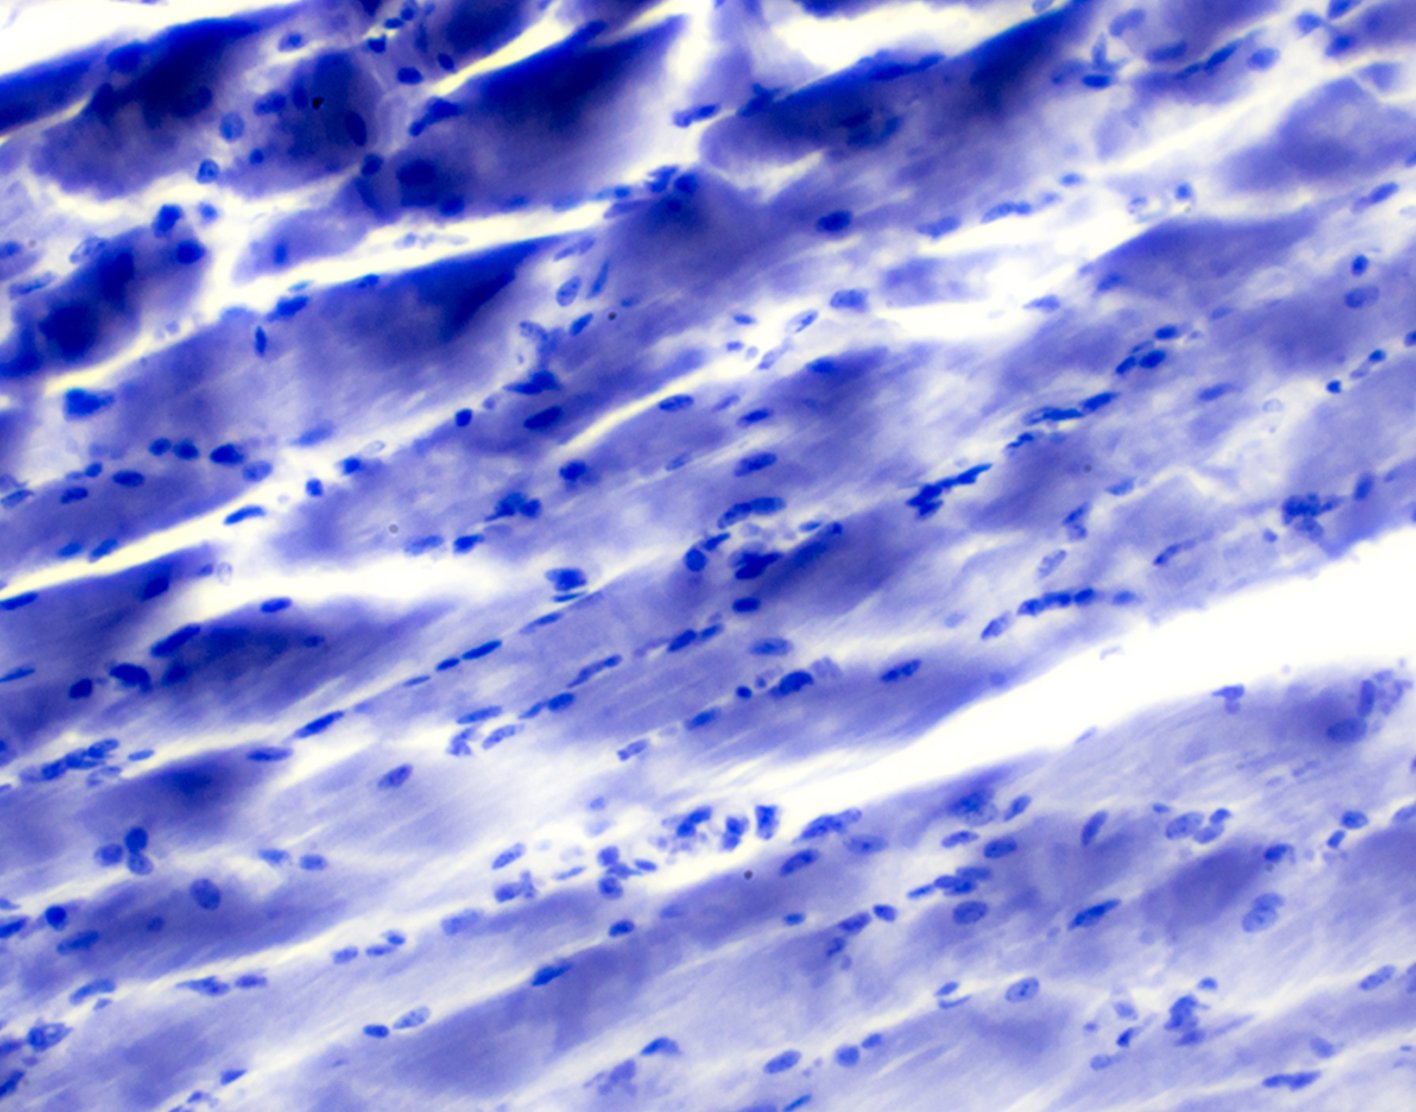

A muscle biopsy is the removal of a small piece of muscle tissue for examination.

After either type of biopsy, the tissue is sent to a lab for examination.

A normal result means the muscle is normal.

What Abnormal Results Mean

A muscle biopsy can help diagnose the following conditions: